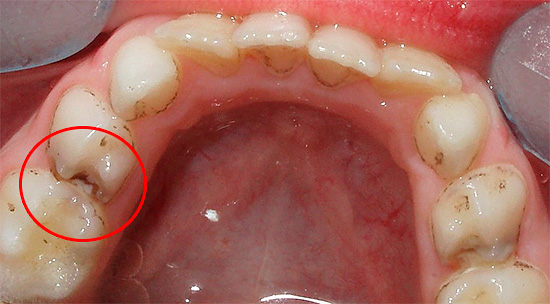

Фото

Существуют разные мнения о лечении кариеса молочных зубов у детей. Некоторые родители считают, что временные зубы не требуют лечения, так как они выпадут. Однако стоматологи подчеркивают важность лечения, даже для временных зубов. Неполеченный кариес может вызывать боль, инфекции и негативно влиять на формирование постоянных зубов.

Лечение кариеса у детей включает профессиональную чистку, фторсодержащие средства и, в некоторых случаях, пломбы. Важно обеспечить безболезненность и комфорт, поэтому стоматологи используют современные методы анестезии и специализированные материалы. Регулярные визиты к стоматологу помогут предотвратить кариес и поддерживать здоровье зубов.

Поверхностная форма характеризуется разрушением зуба до эмалевой границы. В зависимости от индивидуальной чувствительности ребенка, жалобы на болевые ощущения могут отсутствовать. Эмаль приобретает оттенок, который варьирует от светло-коричневого до черного.

Средней принято считать той формой, на которую родители уже самостоятельно обращают внимание и понимают, что настало время лечения. Здесь возникают жалобы на боль от раздражающих веществ и температурных воздействий, а также появляется дырка, которая затрагивает эмаль и дентин. Цвет полости зависит от того, острое или хроническое течение имеет заболевание.